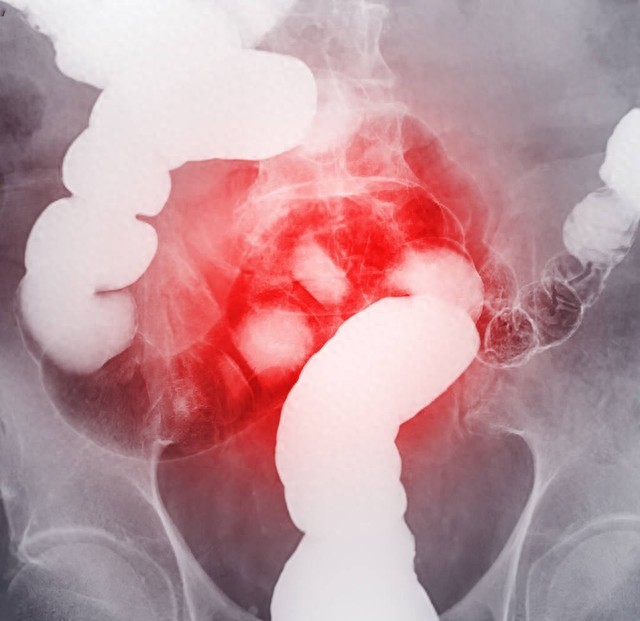

乙状结肠癌能活多久